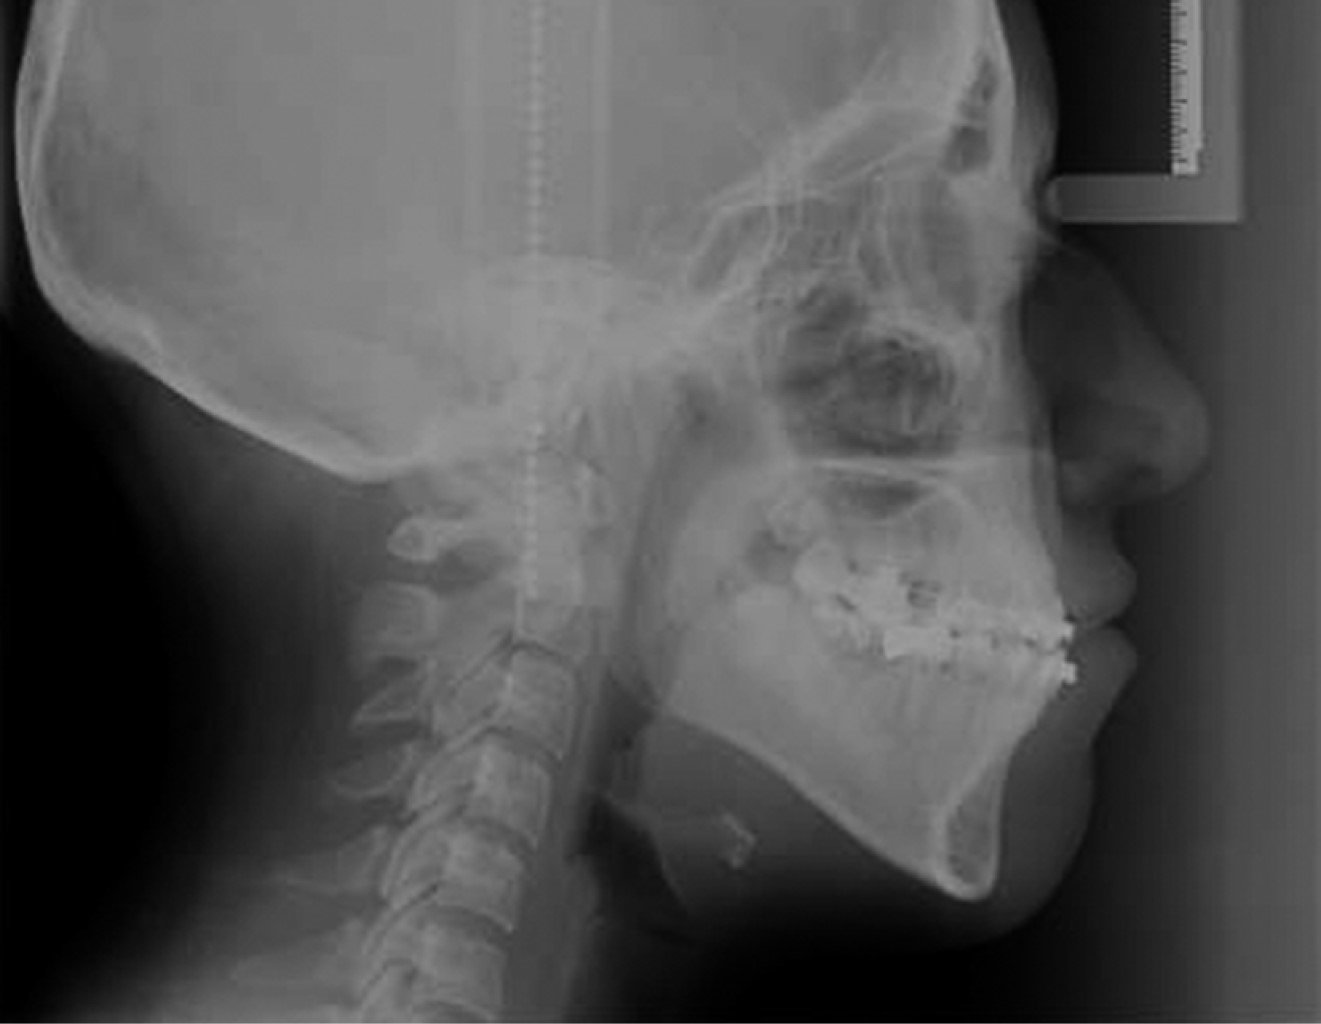

After 12 months the case was reevaluated with the taking of study and work models, lateral and posteroanterior radiography, and orthopantomography, and together with the Surgery Department of DEPeI, UNAM, the orthognathic surgery was programmed (Figure 8).

Presurgical 0.019" × 0.025" stainless steel surgical arches with crimpable hooks were placed. The surgical procedure consisted of bilateral branch sagittal for correction of laterognathia, mandibular retroposition, and maxillary impaction for correction of vertical excess. Eight 8 mm fixation screws were used, three on each side. Seven days after surgery, intermaxillary elastics were placed to achieve adequate seating and prevent the muscle force from generating undesirable movements. These elastics had a class II vector (Figure 9).

The treatment was completed in 23 months, in which the profile was improved, the gingival smile was eliminated, providing facial harmony (Figure 12). The crossbite was eliminated leaving a more stable case, providing an adequate dental harmony, class I canine, and bilateral molar. It was possible to center the dental midlines, improve the shape of the arches, and vertical and horizontal overbite (Figure 13). The dental inclinations were improved and skeletal class I was achieved (Figure 14). A circumferential retainer was placed to improve the occlusal set. After two months, the occlusal adjustment was performed (Figure 15). The changes obtained can be observed facially (Figure 16), occlusally (Figure 17), and radiographically (Figures 18 and 19).

Figure 9

Figure 19